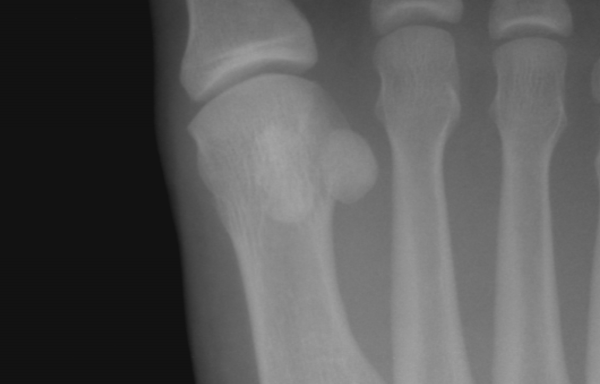

Комплекс сочленений Лисфранка

Сесамовидная кость в дистальном конце первой плюсневой кости

• Неправильное выравнивание второго предплюсневого сустава — общая черта переломов-вывихов Лисфранка. На передне-заднем виде рентгена виден латеральный сдвиг основания второй плюсневой кости и диастазис более 2 мм между основаниями первой и второй плюсневой костей. Рекомендуется сделать рентген в весовом положении, чтобы поврежденная сторона могла быть сравнена с противоположной стороной.[3]

• Перелом сесамовидной кости отображается на рентгене как неровное пространство между частями кости. Ровное разделение двух костей, видимое на рентгене, является нормой у примерно 10% населения.